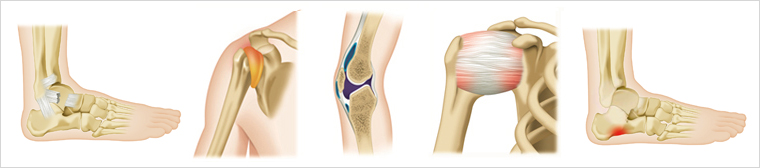

지속적인 운동은 심신을 건강하게 해주지만 무리하거나 외부 충격이 세게 가해지면 상해의 위험이 따르기도 합니다. 골프처럼 동작의 반경이 넓거나 축구처럼 근육과 뼈에 강한 힘이 가해지는 경우, 또 마라톤처럼 지구력을 요하는 운동일수록 상해의 위험이 커집니다. 대표적인 스포츠상해로는 허리, 무릎, 발목 등의 염좌 및 인대손상, 연골손상, 점액낭염, 회전근개손상 등이 있습니다.

- 염좌 : 흔히 ‘삐었다’고 말하는 증상으로 뼈와 근육을 연결하는 인대의 손상 및 파열

- 점액낭염 : 관절의 마찰을 줄이기 활액을 분비하는 무릎과 어깨의 점액낭에 염증 발생

- 회전근개손상 : 어깨관절을 움직이는 회전근개의 손상으로 움직일 수 없을 정도의 통증발생

- 족저근막염 : 발바닥의 얇은 막에 염증이 생기는 질환으로 마라톤 등의 운동에 의해 발생